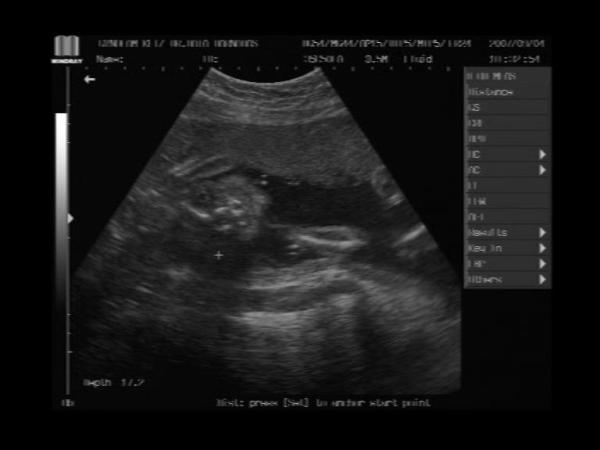

És a bébi 24 hetesen:

Kép Ha jól megnézitek,ez az arca